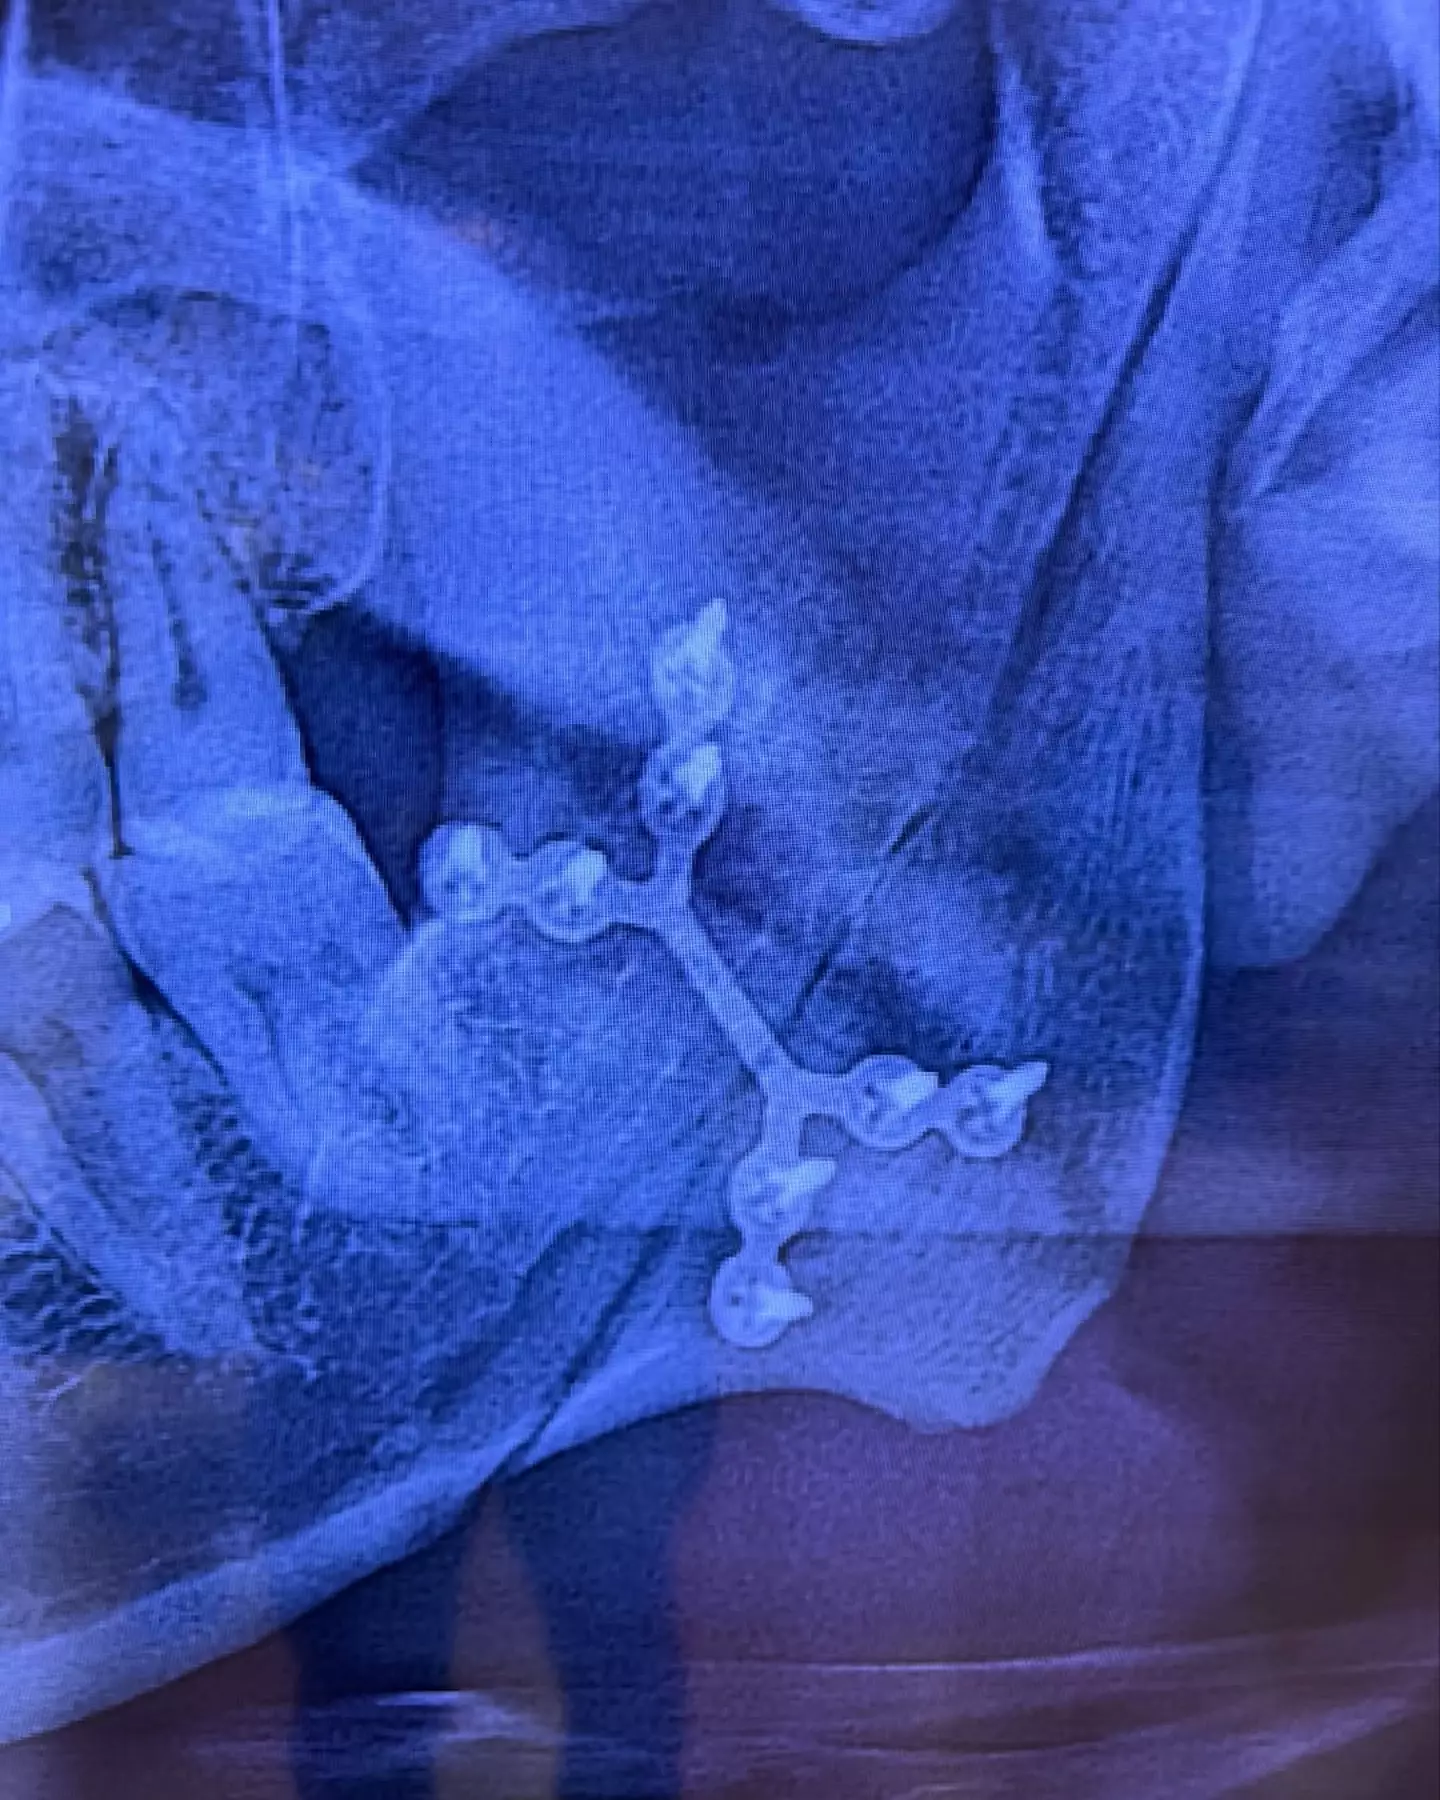

The 52-year-old Aussie star, who was the singer of the pop duo Savage Garden back in the 90s, took to Instagram last Friday (18 April) to share two photos of himself - the first being a selfie showing the extent of his injuries and the second revealing an X-ray scan of his broken jaw.

"The blunt force trauma was so severe it snapped my left jawbone in half," Hayes continued. "I woke up in a pool of blood, terrible pain in my left side of my head and with nine teeth shattered.

Hayes noted that doctors scanned for and ruled out heart issues and 'anything neurological', adding: "I was scheduled for emergency reconstructive surgery and this happened on March 21st.

"The incredible surgeons inserted a titanium brace to re-connect my jaw bones and my mouth was wired shut for a minimum of eight weeks while the left jaw bone could heal."